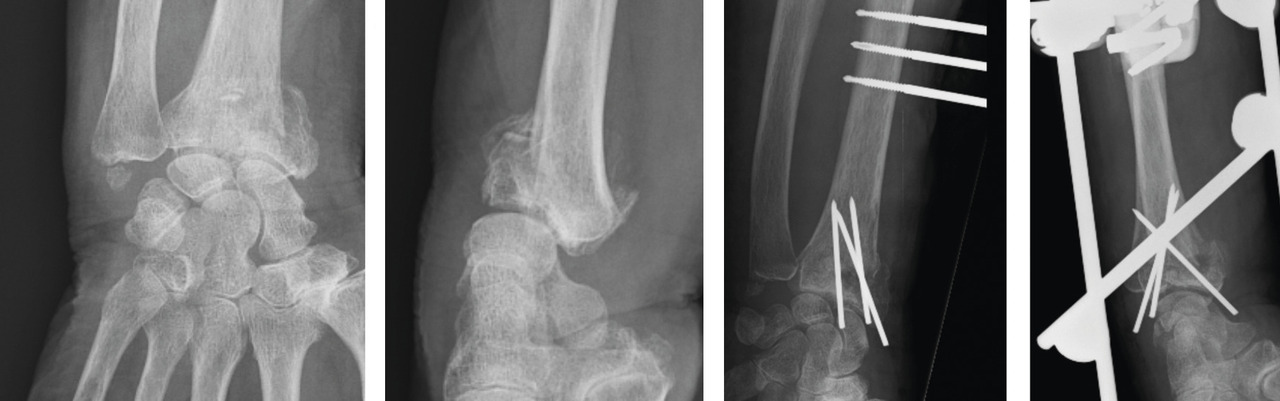

Le traitement chirurgical, justifié en cas de déplacement non tolérable, repose sur 3 modalités pratiques distinctes : l’embrochage percutané, les plaques palmaires vissées, et le fixateur externe radiométacarpien, à ne jamais utiliser seul. Ces traitements remplissent le double rôle de réduction et de stabilisation de la fracture jusqu’à consolidation.

La mise en place des broches percutanées sont habituellement introduites dans le foyer de fracture, en arrière du radius, puis inclinées vers le bas pour réduire la bascule dorsale de la glène radiale et sont finalement fichées dans la corticale antérieure, épaisse, pour stabiliser la réduction obtenue. Il s’agit d’un embrochage « intrafocal » (dans le foyer de fracture). Une ou deux broches styloïdiennes dans le plan frontal complètent le montage. La bascule antérieure du fragment distal, la présence de refends articulaires, et la comminution métaphyso-épiphysaire sont indispensables à évaluer avant de proposer ce type de traitement et constituent des contre-indications relatives (fig. 12).

La mise en place de plaques palmaires nécessite un abord chirurgical antérieur et reste techniquement délicat, en particulier pour positionner la plaque en hauteur et pour la longueur des vis dont l’excès peut endommager les tendons extenseurs. L’indication phare reste les fractures métaphysaires à déplacement antérieur ou les comminutions métaphysaires étendues (fig. 13).

Enfin, le fixateur externe ne doit pas être utilisé seul car une traction excessive est un facteur de risque d’algo­neurodystrophie. Il doit être ajouté comme moyen de protection d’une ostéosynthèse par broche ou plaque précaire. Son rôle est de neutraliser les contraintes en compression sur l’extrémité inférieure du radius en cours de consolidation (fig. 14).